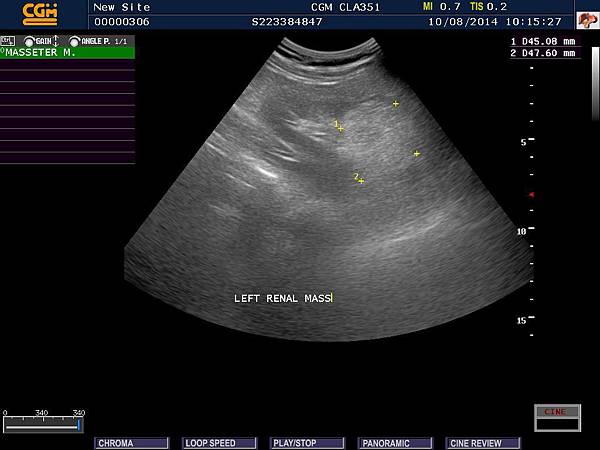

前陣子接到一份回診單,看完之後著實鬆了一口氣,另外,也想紀錄這一件事情做為將來衛教資料,患者是一位年輕女性,剛好有一天中午來到門診,主述下腹部疼痛,因為患者有便秘病史,問診與理學檢查後,考慮或許是便秘所造成,想說開一些軟便藥物就可以了,不知那一天,如何心血來潮 ( 或許是醫師的直覺吧 ),想說超音波看一下是否有什麼異常,結果 ...,竟然發現兩側腎臟腫瘤,如圖:

腎臟腫瘤 A

當下甚怕自己中午還沒吃,血糖有些低,是否有所誤判,便囑咐患者過幾天回診,再確定一下,數天後,患者表示狀況改善,超音波顯示兩側數個4至7公分的腫瘤,當下想說很有可能是惡性腫瘤,趕快開立轉診單,後續追蹤吧 ! 但心中總有些許惆悵,想說這麼年輕小姐將來如何呢 ? 腫瘤是否能摘除乾淨嗎 ? 是否需要長期洗腎丫 ? 今晚終於接到回診單啦 ! 護士小姐、藥師與我都懷者忐忑的心情揭曉答案,整體報告顯示腎功能正常與懷疑兩側良性血管肌肉脂肪腫瘤,接著馬上把消息告訴患者,分享喜悅的心情。